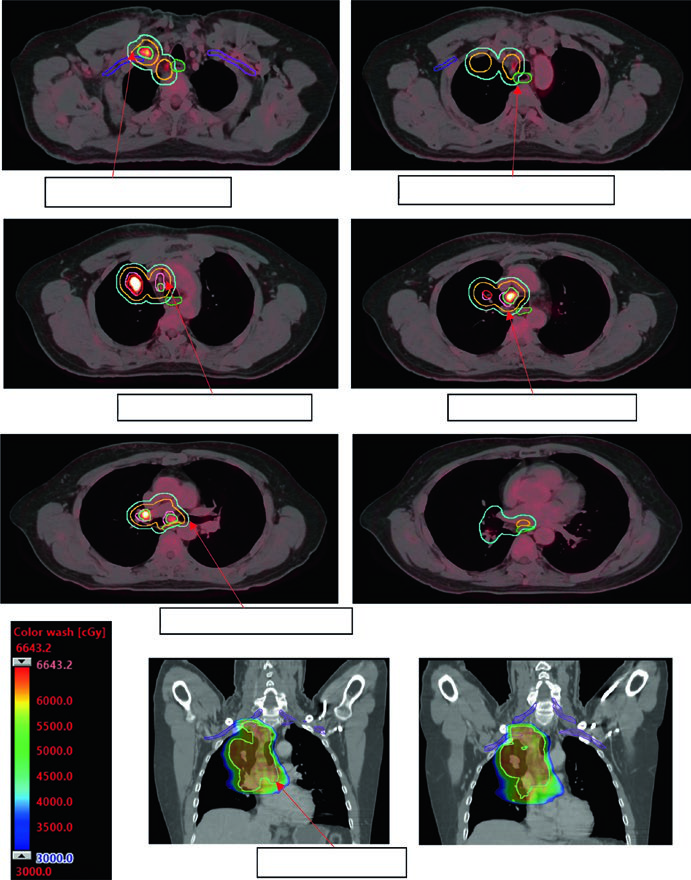

A dose padrão para CPNPC estádio II-III com quimioterapia concomitante é 60 Gy em 30 frações (2 Gy/fx). Doses de escalada acima de 60 Gy não demonstraram benefício em ensaios randomizados e aumentaram toxicidade. O GTV inclui tumor primário e linfonodos acometidos visíveis em TC ou PET.

A Figura 13.3 do texto ilustra um caso cT1cN3M0 IIIB: tumor no LSD com linfonodo hilar direito, subcarinal, paratraqueal e SCV direita acometidos. O plano de 60 Gy/30fx cobre todos os sítios PET-positivos com exclusão das cadeias eletivas contralaterais. A Figura 13.4 mostra um caso cT4N3M0 IIIC com SCV bilateral comprometida e síndrome de veia cava superior, exigindo campo que inclui mediastino superior bilateral.